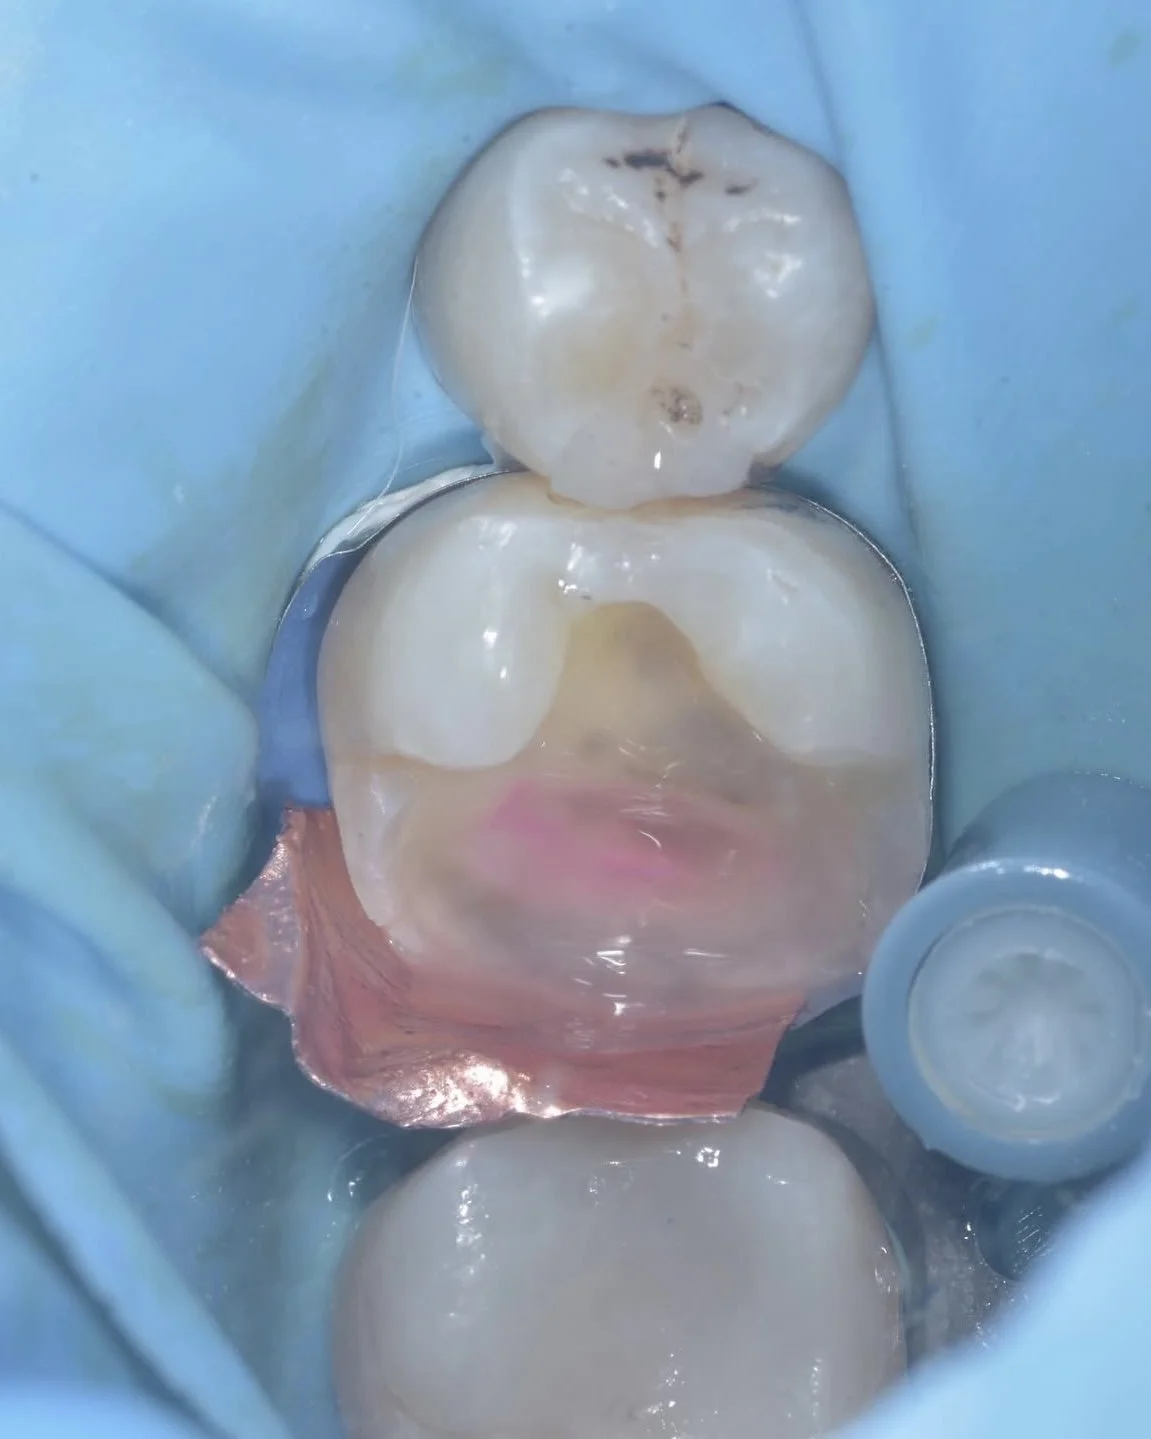

Here are two examples of caries removal endpoints (CRE) in this case by Dr. Davey Alleman, DMD. Complete caries removal was possible on the left tooth, while the right tooth required partial caries removal to preserve the pulp vitality.

This case by Dr. Davey Alleman, DMD shows the process of removing caries around the pulp to create a caries-free peripheral seal zone.